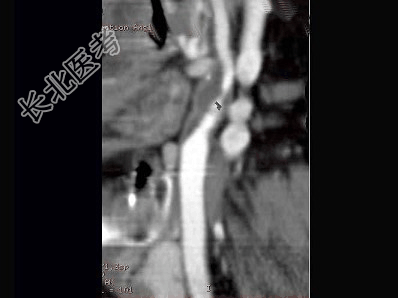

- 多项选择题男,65岁, 近半年时常突发性头晕,CT三维重建如图, 正确的描述或结论是 ( )

A、颈内动脉起始段有一长约3.0cm的狭窄段

B、狭窄段可见低密度不强化血栓影

C、狭窄段管壁见点状致密钙化影

D、拟为颈内动脉粥样硬化性狭窄

E、拟为颈外动脉粥样硬化性狭窄